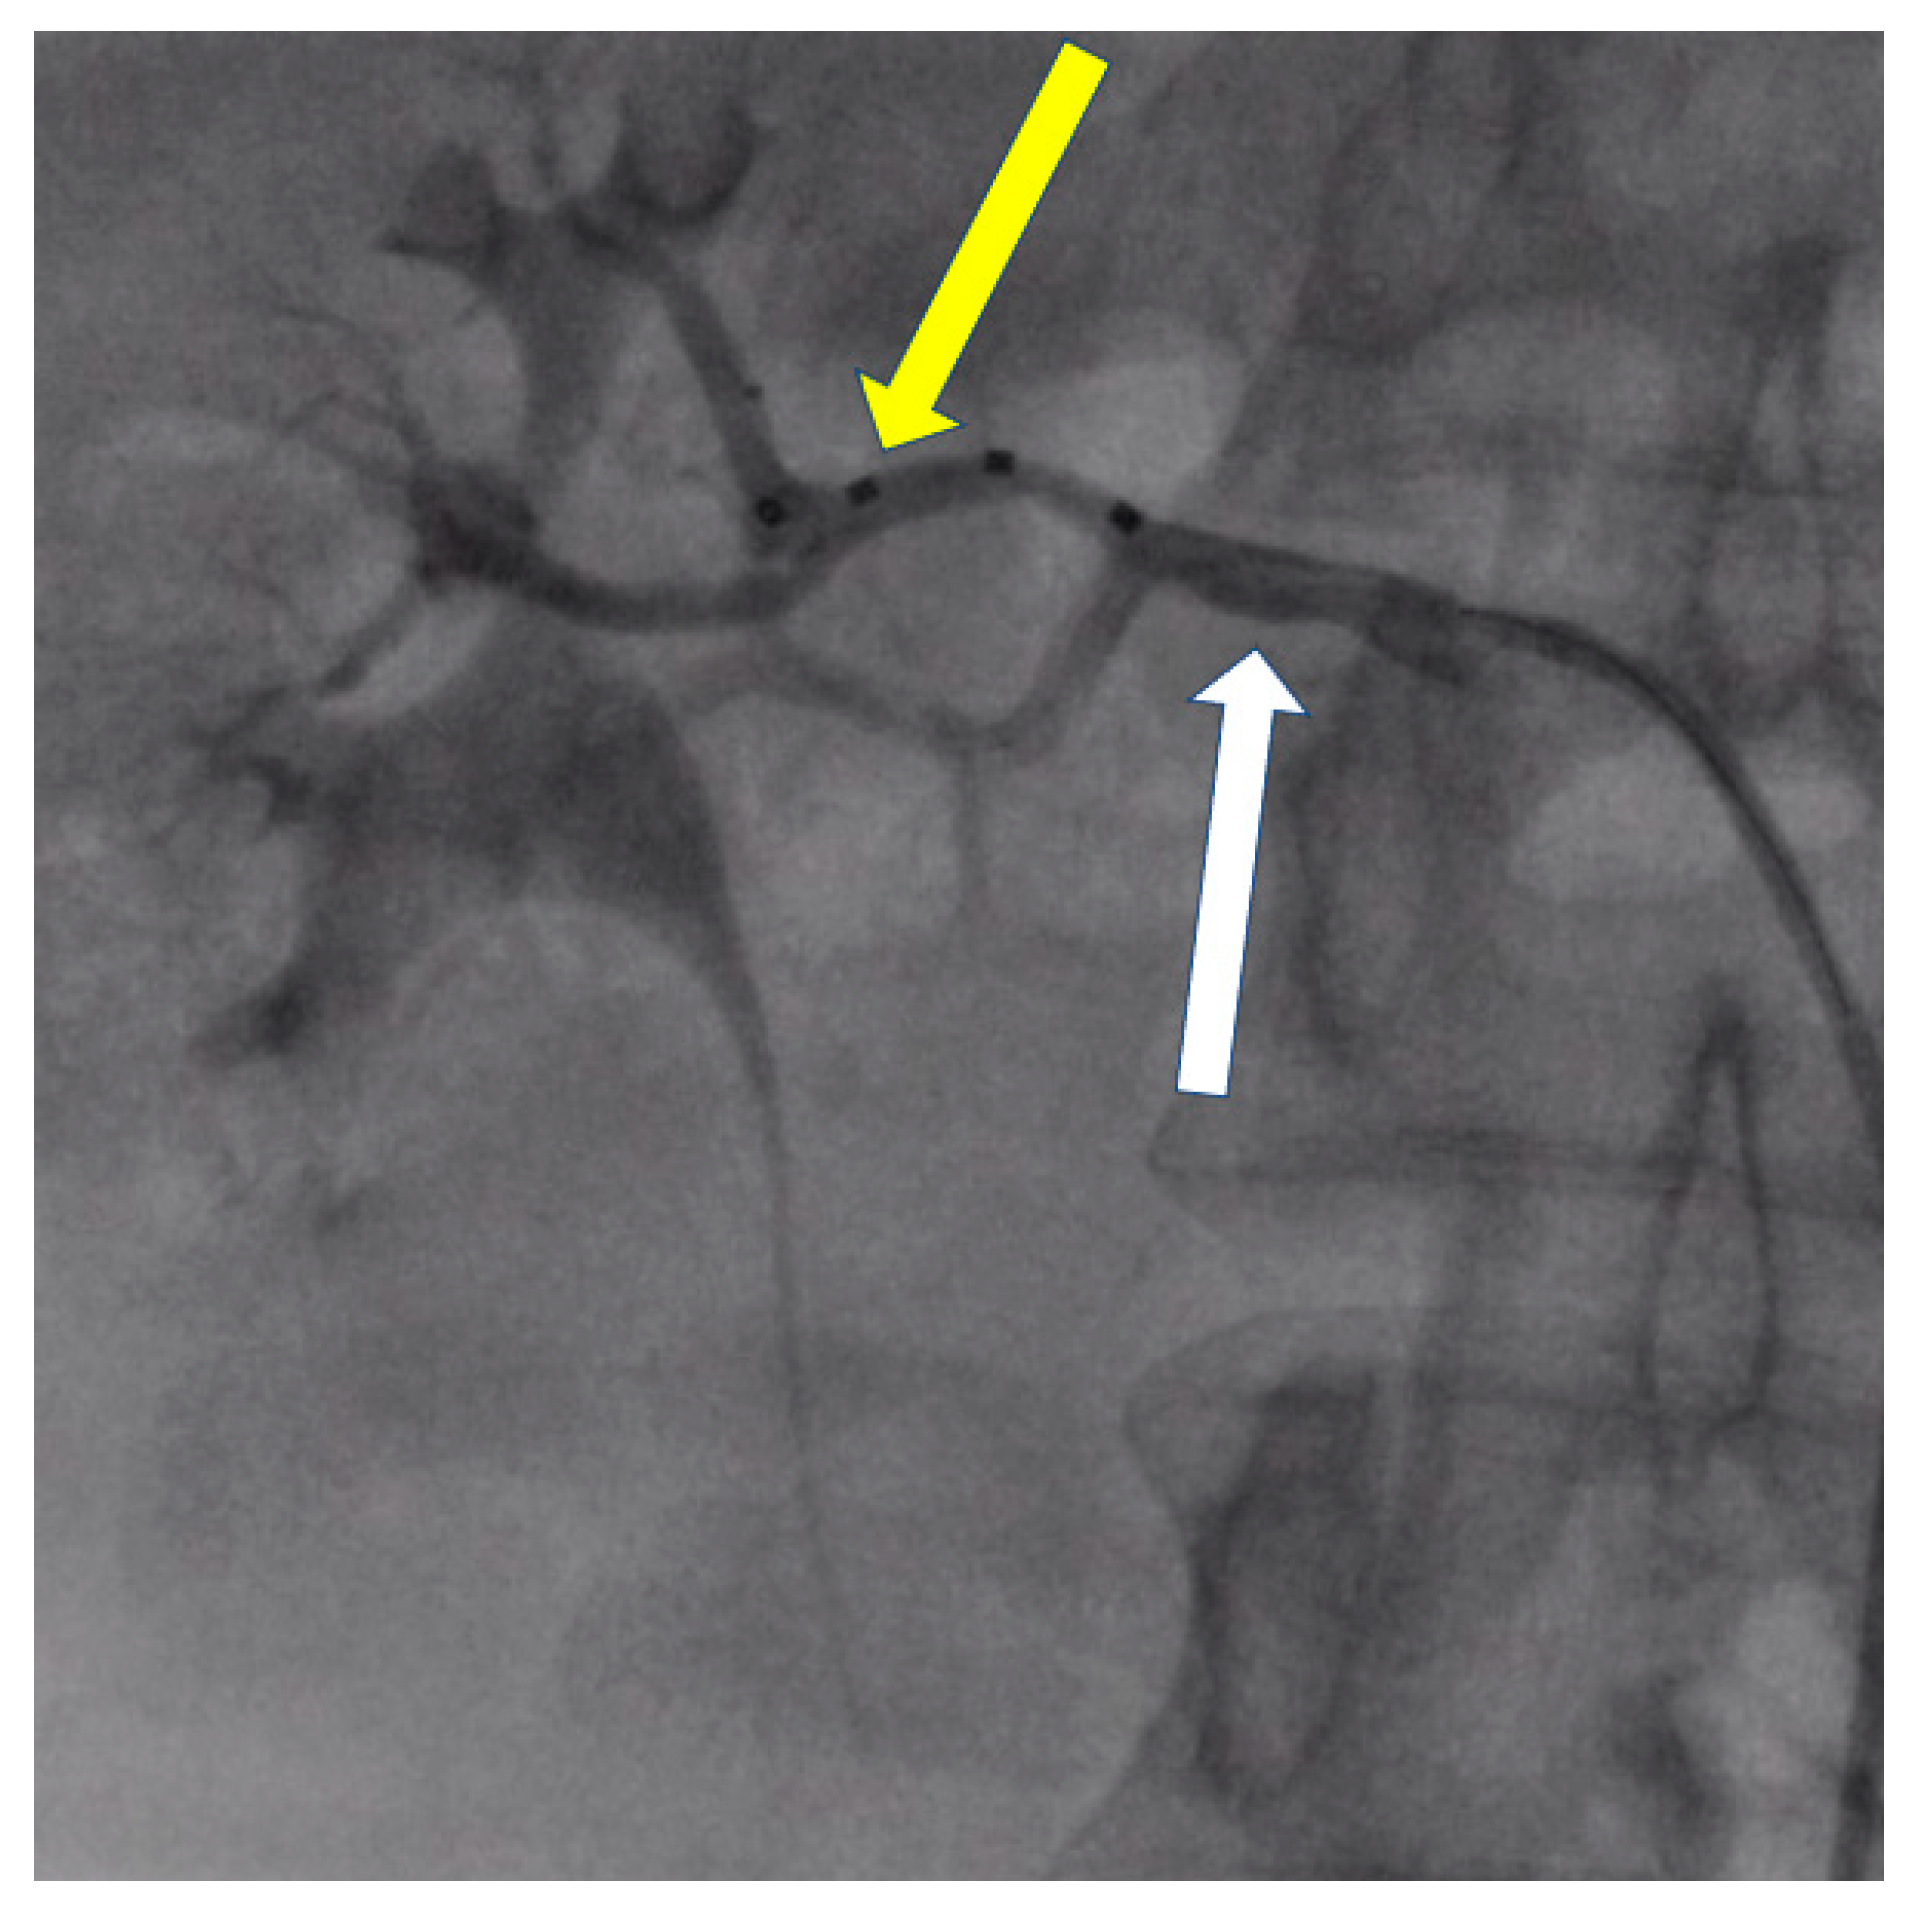

- Możeńska, O.; Rosiak, M.; Gziut, A.; Gil, R.J.; Kosior, D.A. First-in-man experience with renal denervation of multiple renal arteries in a patient with solitary kidney and resistant hypertension. Pol. Arch. Intern. Med. 2017, 127, 60–62. [Google Scholar] [CrossRef]

- Atas, H.; Durmus, E.; Sunbul, M.; Mutlu, B. Successful accessory renal artery denervation in a patient with resistant hypertension. Heart Views 2014, 15, 19–21. [Google Scholar] [PubMed]

- Bertoldi, L.; Latib, A.; Piraino, D.; Regazzoli, D.; Sticchi, A.; Pizzetti, G.; Camici, P.G.; Colombo, A. Renal denervation in a patient with two renal accessory arteries: A case report. Blood Press 2013, 22, 325–328. [Google Scholar] [CrossRef] [PubMed]

- de Leon-Martinez, E.P.; Garza, J.A.; Azpiri-Lopez, J.R.; Dillon, K.N.; Salazar, L.O.; Canepa-Campos, F.; Rousselle, S.D.; Tellez, A. Safety and Clinical Outcome of the Delivery of Radiofrequency Nerve Ablation Therapy in a Renal Artery of Unusual Anatomy. High Blood Press Cardiovasc. Prev. 2015, 22, 445–448. [Google Scholar] [CrossRef]